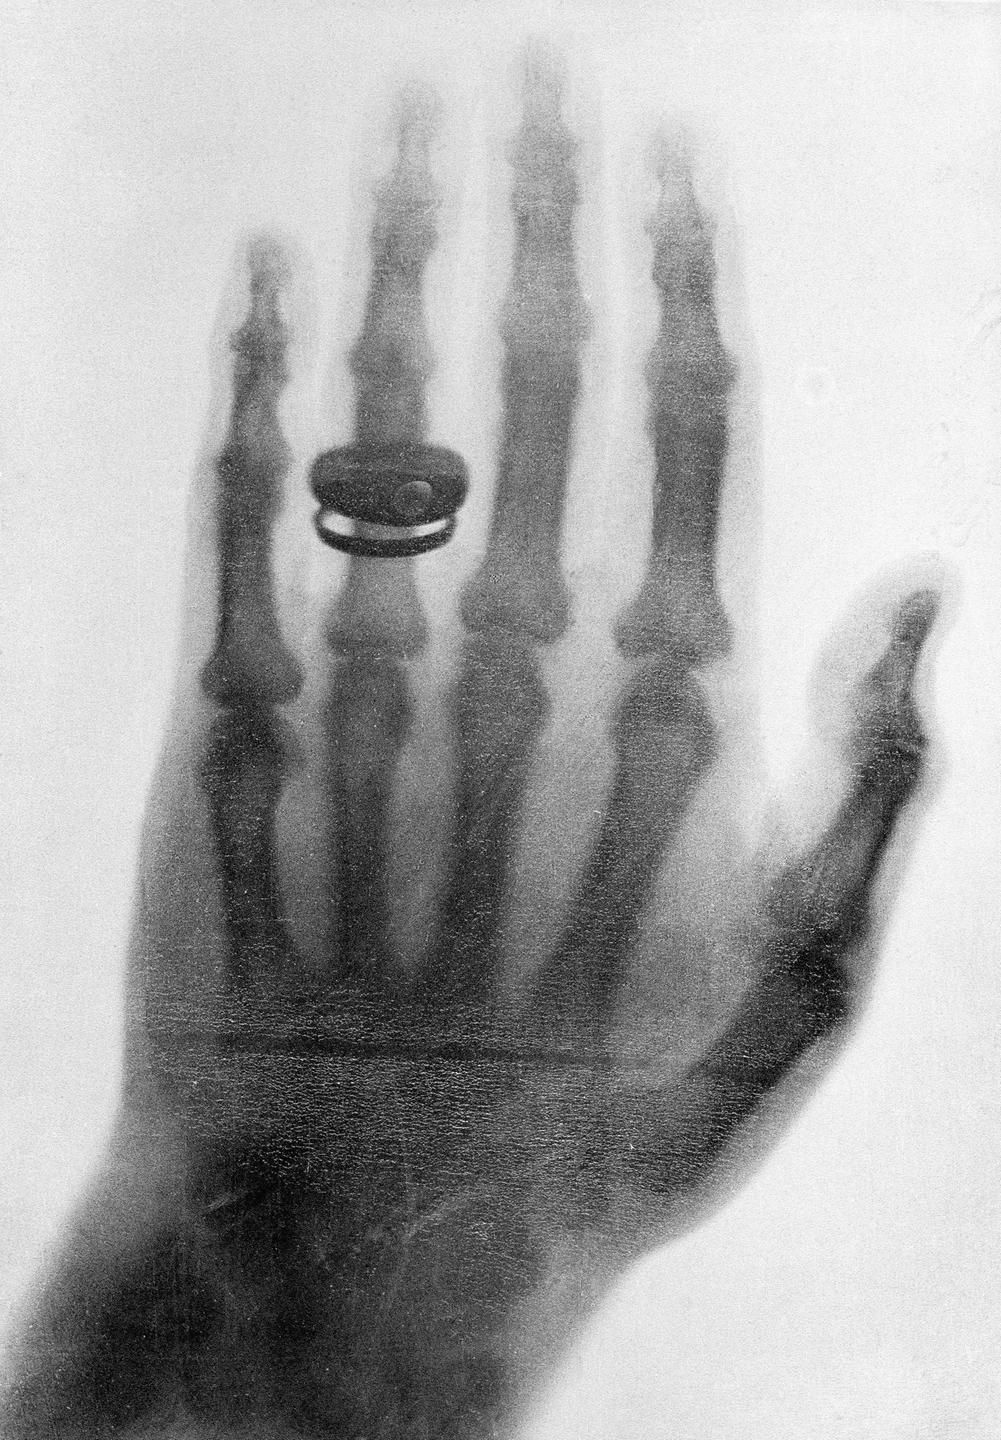

File: röntgen.jpg (283 KB, 1001x1440)

283 KB

283 KB JPG

>>532694264

u know you dont need uranium to make pictures like these? took a while longer to find microwaves

>>